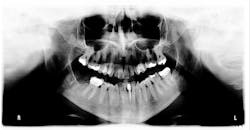

Figure 1: Panoramic x-ray

One of the most difficult things we encountered in treatment planning was obtaining radiographs, due to the lack of elasticity of the skin. Diane was unable to tolerate any stretching of her cheek and lips to accommodate even a size one pediatric sensor. I was able to get less-than-ideal bitewings and manipulate the area for one periapical film. She was then referred back to her general dentist to obtain a panoramic film, since our office is only capable of taking digital full-mouth series using the sensor or CBCT images.

Her periodontal probing depths ranged from 2 mm to 6 mm, with as much as 4 mm of recession noted in some areas. Tooth No. 19 had a fractured off DL cusp to the gumline with decay close to the nerve; No. 29 had deep DO decay that would require endodontic treatment, buildup, and a crown to repair or possibly extraction; and No. 31 was unrestorable with buccal decay to the nerve, through the furcation, and at the bone level (figures 1–6). Faced with that treatment plan, she would also need four quads of scaling and root planing with anesthetic. We were able to coordinate the schedule to extract No. 31 directly after her periodontal treatment while she was still anesthetized.